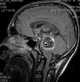

CSF-intensity brainstem lesion

A brain tumor occurs when abnormal cells form within the brain. There are two main types of tumors: cancerous (malignant) tumors and benign (non-cancerous) tumors. [Source: Wikipedia ]